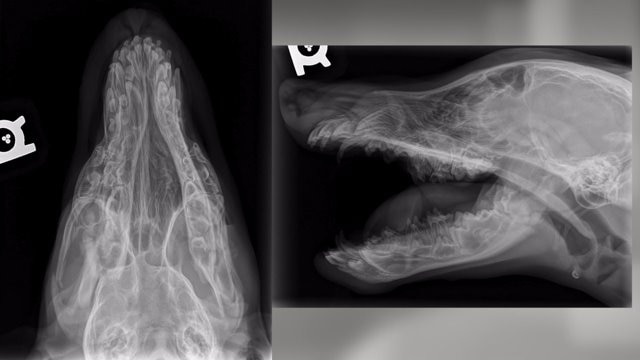

Puppy Abuse Arrest